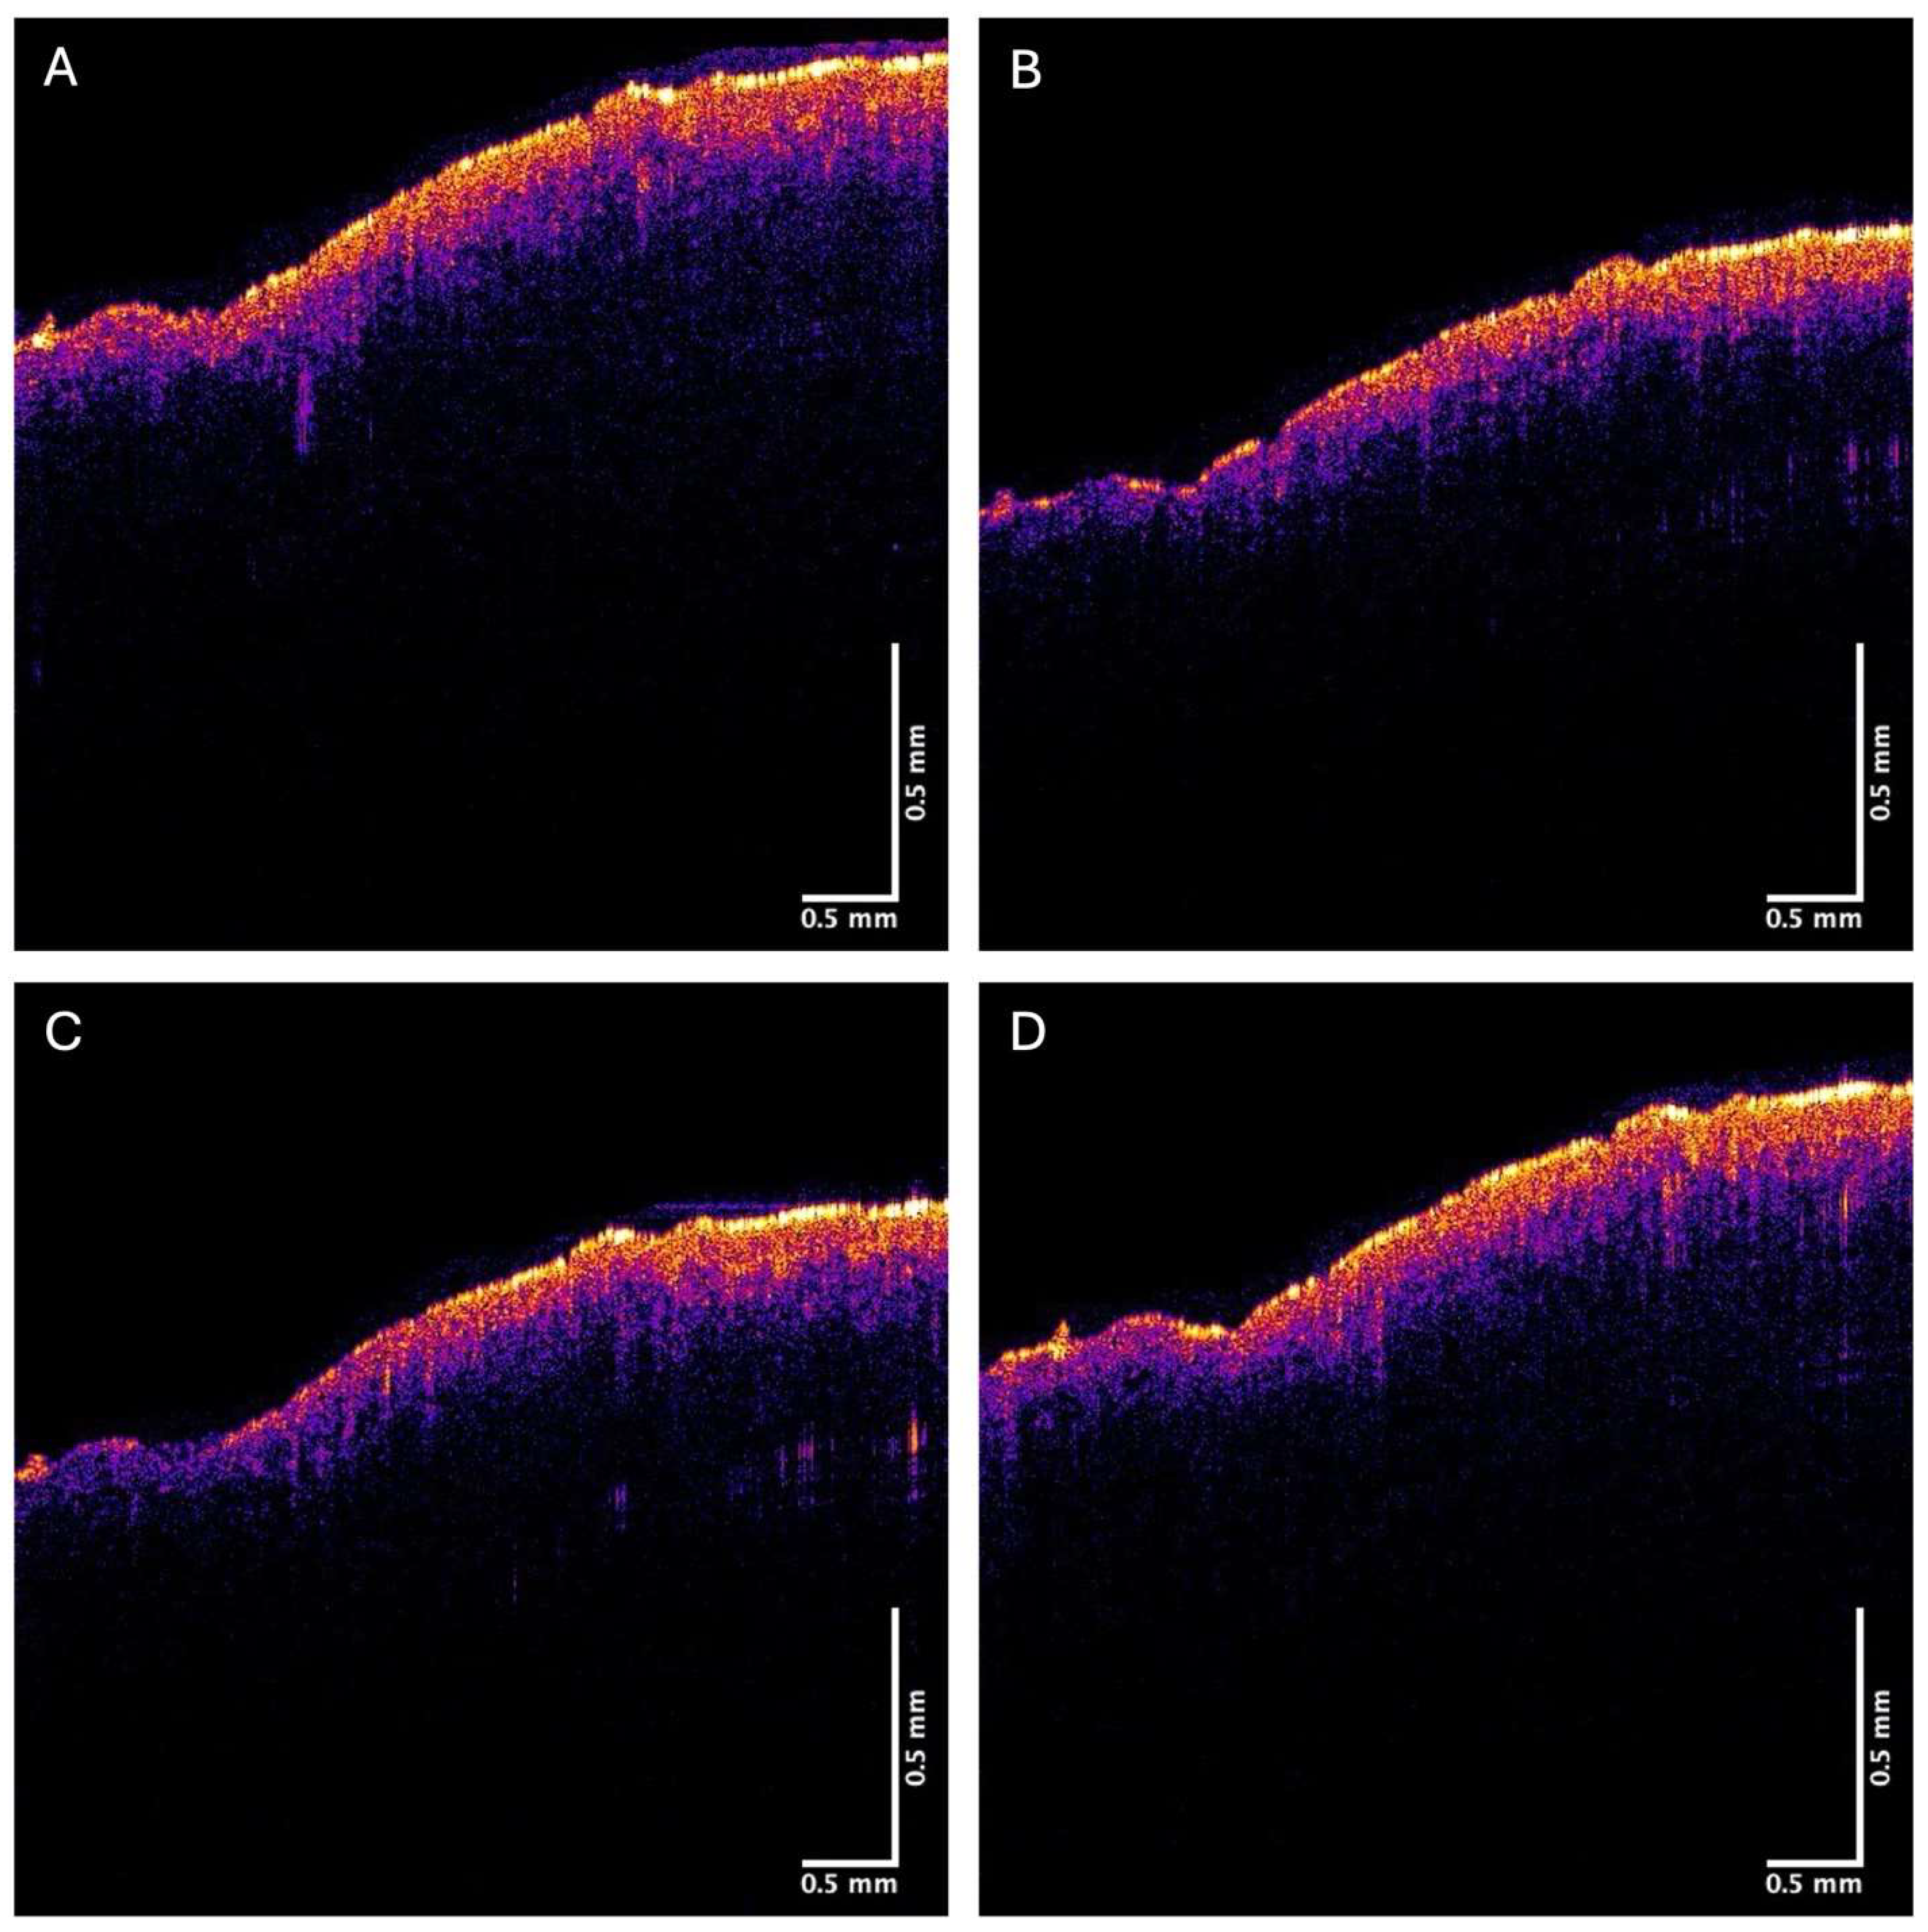

2.1. OCT Image Collection

3. Results